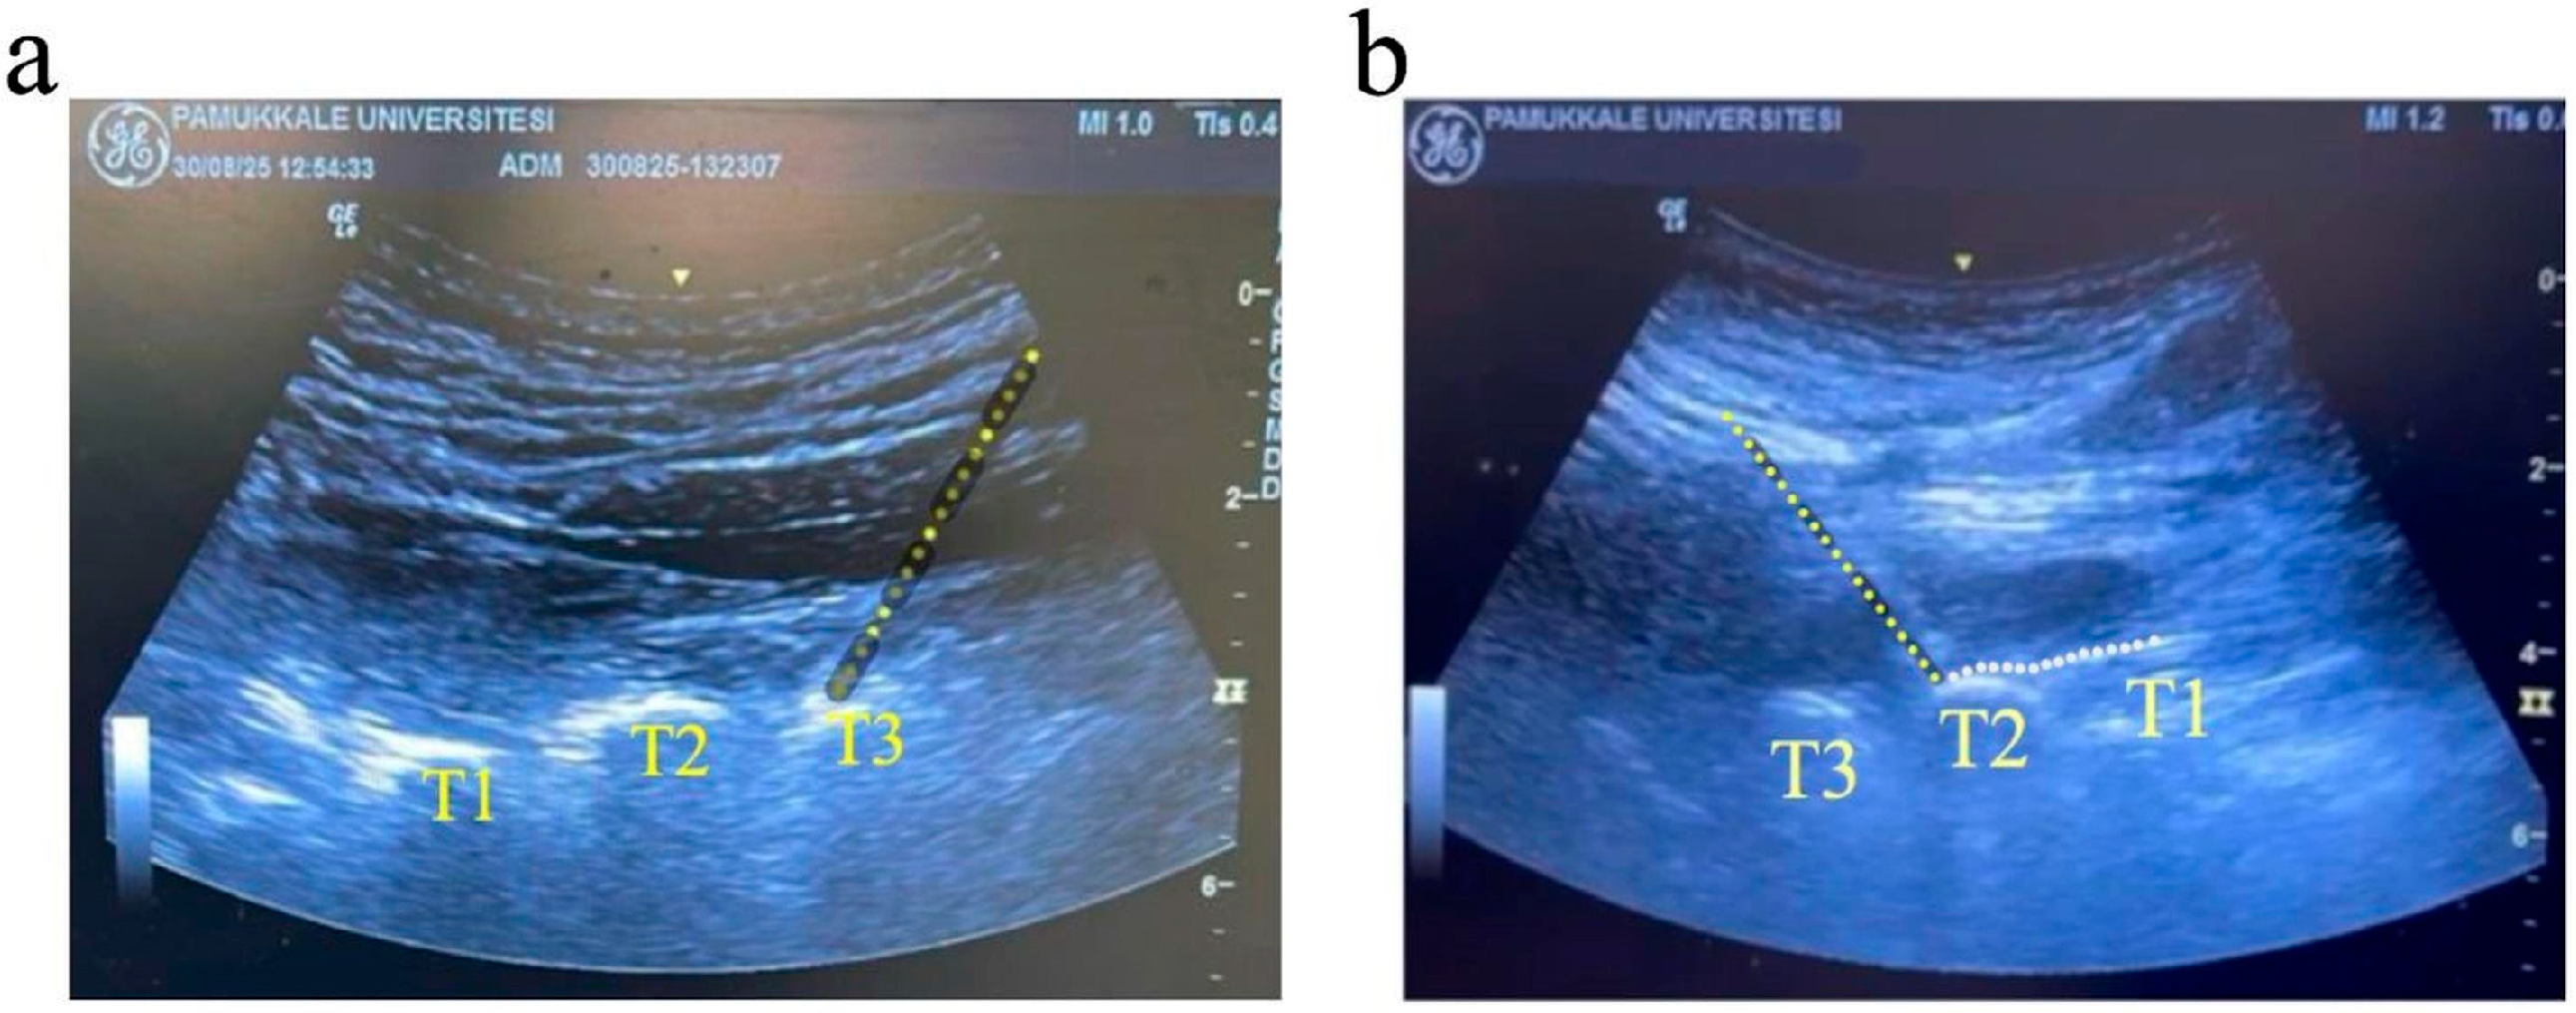

2.4. High Thoracic ESPB Procedure